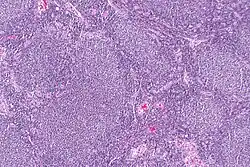

| Micrograph of a follicular lymphoma, showing the characteristically abnormal lymphoid follicles that gave the condition its name. H&E stain. | |

Follicular lymphoma (FL) is a cancer that involves certain types of white blood cells known as lymphocytes. This cancer is a form of Non-Hodgkin Lymphoma and it originates from the uncontrolled division of specific types of B-cells (centrocytes and centroblasts). These cells normally occupy the follicles (nodular swirls of various types of lymphocytes) in the germinal centers of lymphoid tissues such as lymph nodes. The cancerous cells in FL typically form follicular or follicle-like structures (see adjacent Figure) in the tissues they invade. These structures are usually the dominant histological feature of this cancer.[1]

The diagnosis of FL depends on examining involved tissues for histological, immunological, and chromosomal abnormalities that are indicative of the disease. FL usually involves enlarged lymph nodes populated by abnormal follicles (see adjacent picture) that when examined histologically contain a mixture of centrocytes or centroblast surrounded by non-malignant cells, mostly T-cells. The centrocytes, which typically outnumber centroblasts, are small to medium-sized B-cell lymphocytes that characteristically exhibit cleaved nuclei; the centropblasts are larger B-cell lymphocytes without cleaved nuclei.[9] Rare cases of FL may show lesions that contain tissue infiltrations dominated by B-cells with features of precursor (i.e. "blast") cells, monocytes, or malignant mantle cells such as those found in mantle cell lymphoma.[1] Immunochemical analyses reveal that these cells generally express B-cell surface markers including the CD10 (60% of cases), CD20, CD19, CD22, and CD79 but not CD5, CD11c, or CD23 cell surface proteins;[2] genomic analyses reveal that these cells contain t(14:18)(q32:q21.3) translocation (85–90% of cases), 1p36 deletions (60–70% of cases), and with far less frequency the other genomic abnormalities listed in the above sections on Pathophysiology and Presentation and course. None of these protein markers or genomic abnormalities are diagnostic for FL, e.g. the t(14:18)(q32:q21.3) translocation is found in 30% of diffuse large B-cell lymphoma and in a small number of reactive benign lymph nodes. Rather, the diagnosis is made by a combination of histological, immunological, and genomic abnormalities.[2] According to World Health Organization (WHO) criteria, follicular lymphoma can be classified morphologically by the relative amount of centroblasts. However, such classification is optional, due to poor reproducibility and little difference in prognosis and treatment, except that a lymphoma with almost only centroblasts may be diagnosed as a diffuse large B-cell lymphoma (DLBCL).[48] The optional classification of follicular lymphoma is as follows:[49]